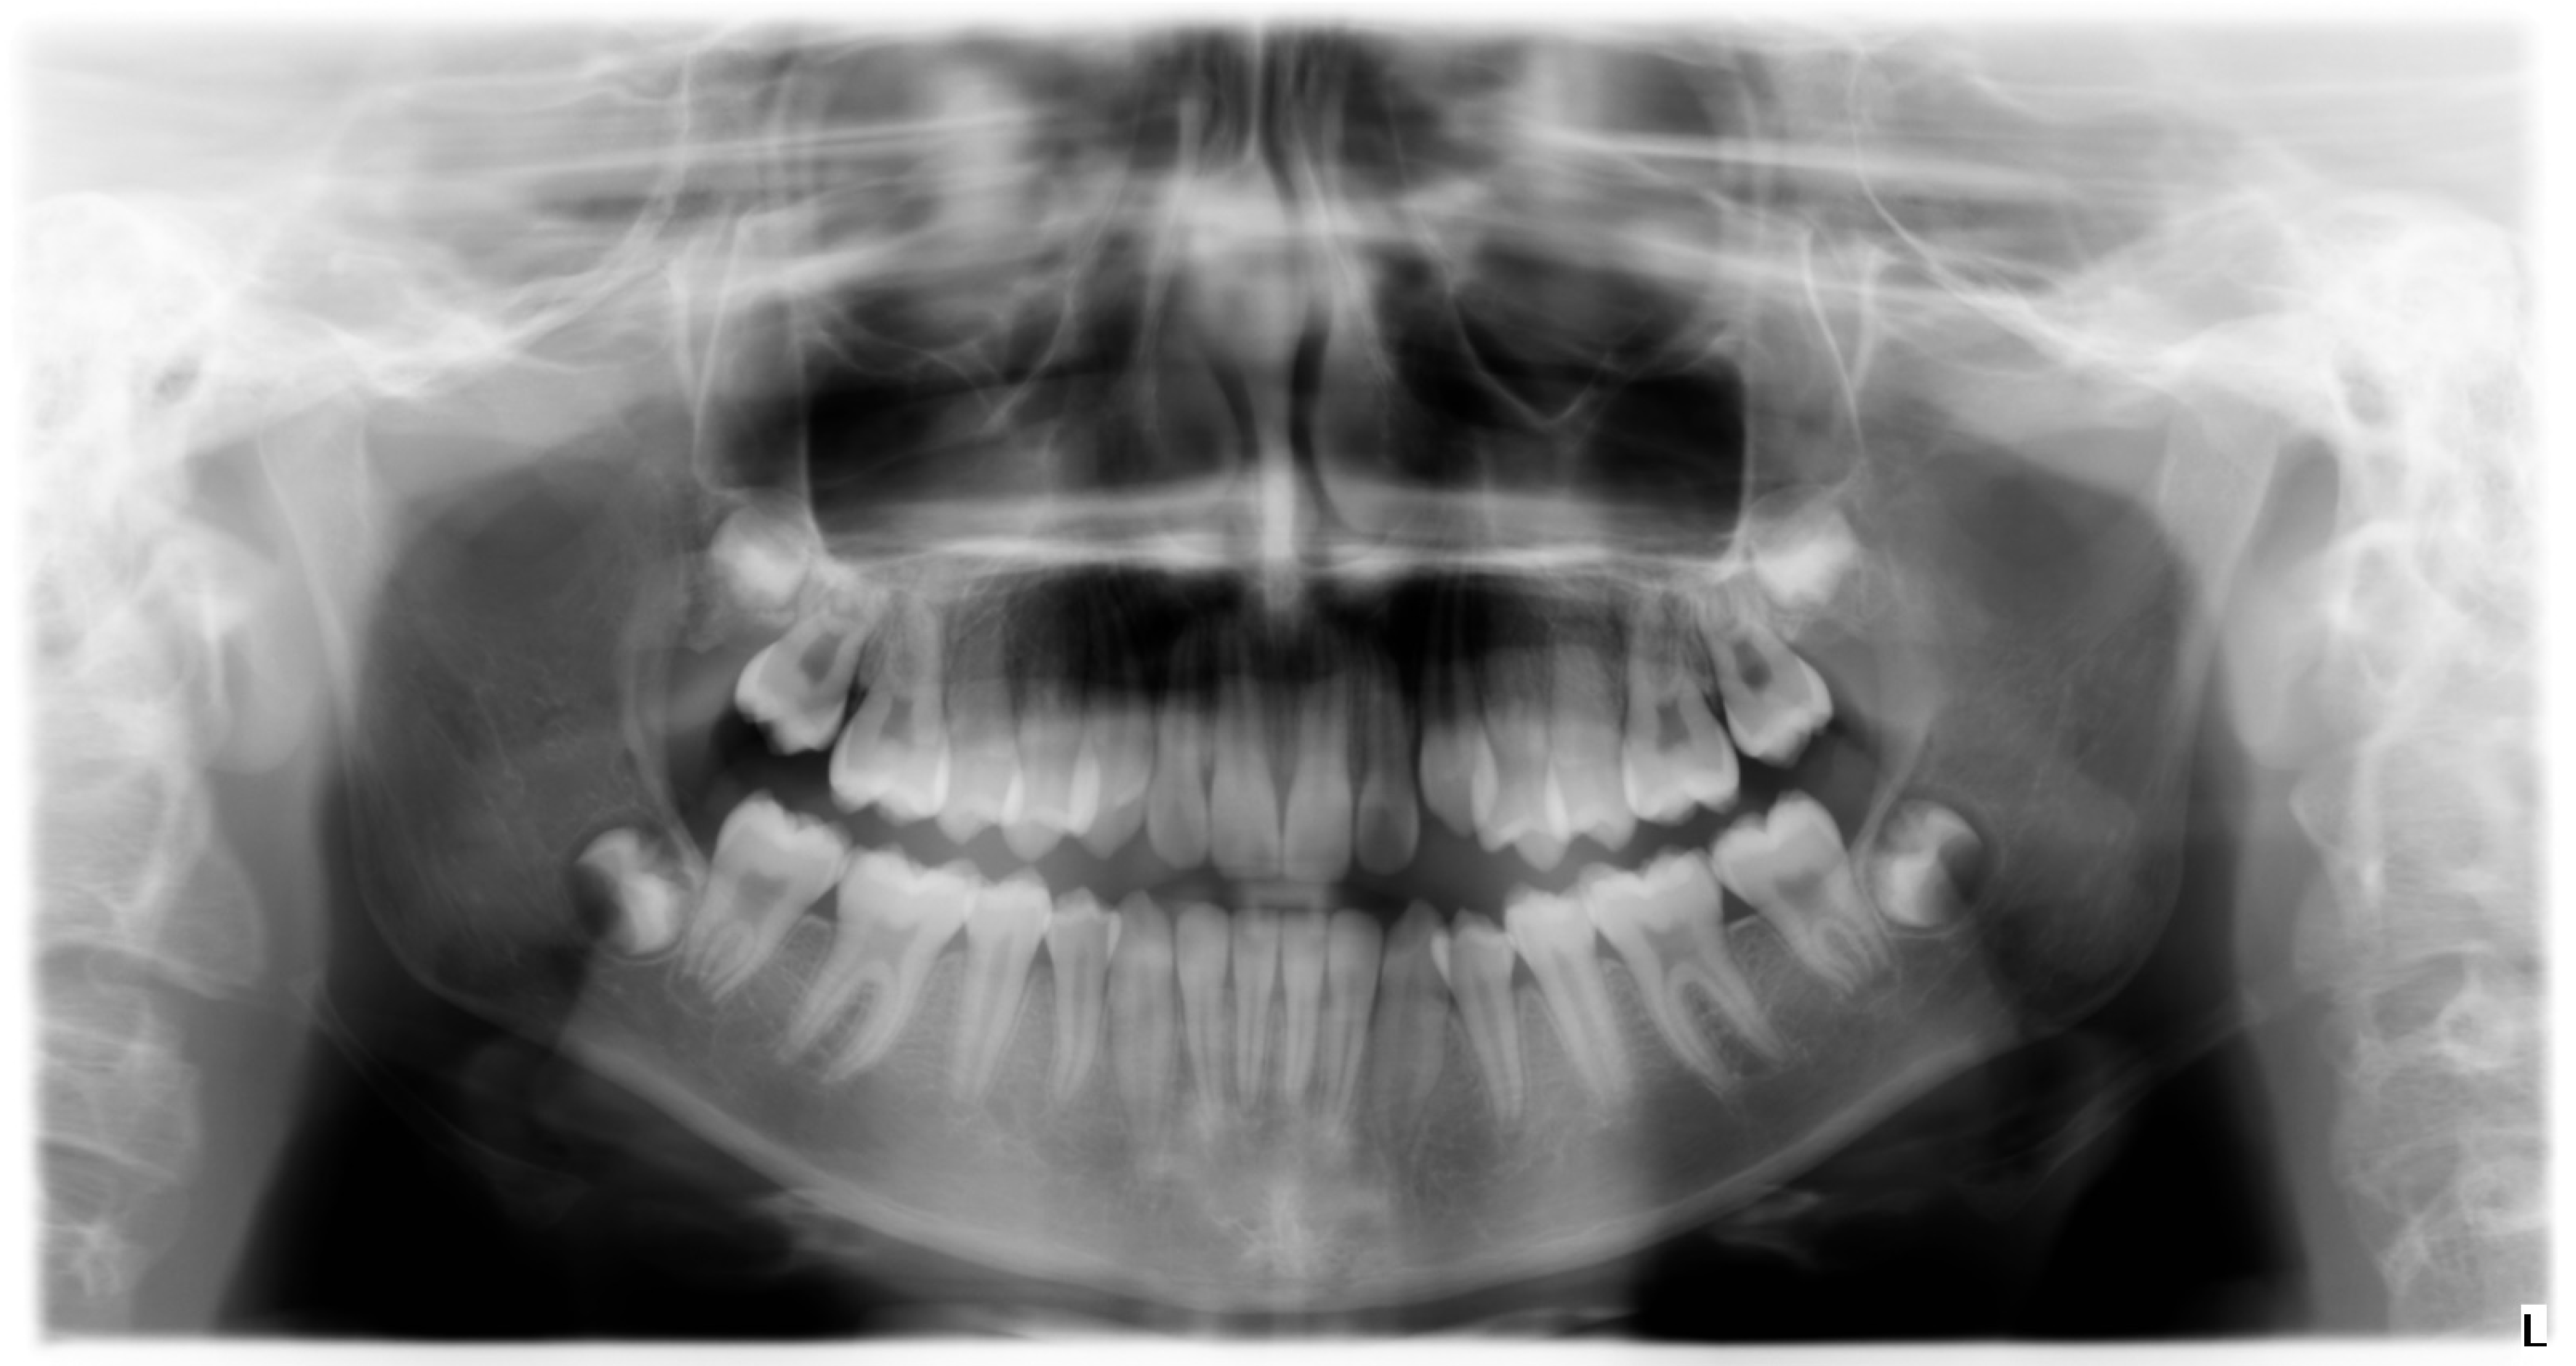

3.1. Clinical Case #1

3.2. Clinical Case #2

3.3. Clinical Case #3

3.4. Clinical Case #4